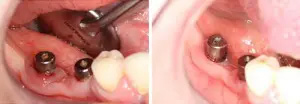

Peri-implant Mucositis